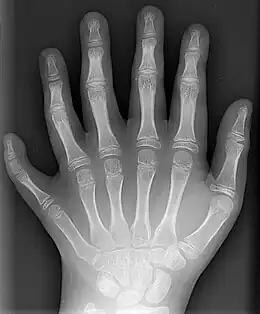

Les doigts (prononcé [dwa][1]) sont les extrémités articulées des mains de l'être humain et de certains animaux — l'expression courante « doigts de pied » désigne les orteils. La présence de doigts caractérise le clade des tétrapodes.

Les cinq doigts de la main sont :

- le pouce[6], essentiel à la préhension ;

- l'index[7], qui indique, pointe, montre ;

- le majeur[8] ou médius[9], le plus grand ;

- l'annulaire[10], qui dans certaines cultures porte l'anneau de mariage parce qu'il est relié au coeur par la Vena amoris ;

- l'auriculaire[11], le plus petit, qui est nommé en fonction de l'oreille (auris en latin).

Ils sont ordonnés, en numération romaine, de I à V à partir du pouce. En musique — piano, guitare, violon, etc. —, pour indiquer le doigté sur une partition, ils sont numérotés en chiffres arabes (1 à 5).

Un doigt est composé de trois phalanges, sauf le pouce et le gros orteil, qui n'en ont que deux[12]. Il s'agit, en partant de la paume, de la phalange, la phalangine[13] et de la phalangette[14].

Les jonctions entre les os du doigt sont nommées articulations interphalangiennes. Celles entre les doigts et la paume de la main sont nommées articulations métacarpo-phalangiennes.